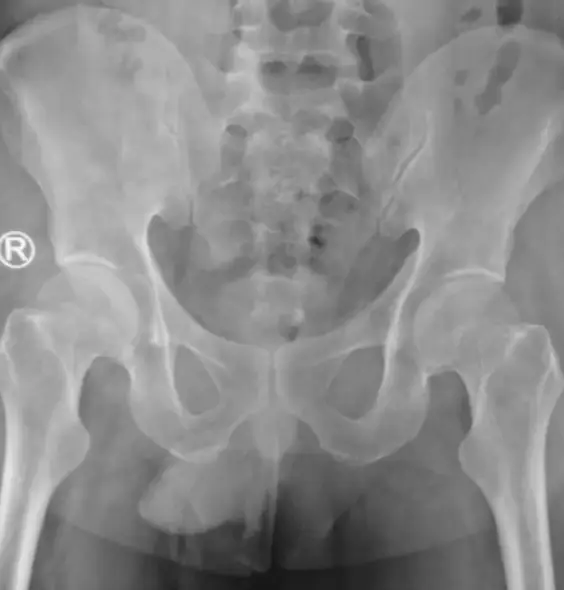

After an unsuccessful first attempt to remove the string, doctors decided to insert a camera into the man's bladder. This showed a 'black bundle of string' which meant that medics were able to use forceps after giving him local anaesthetic.